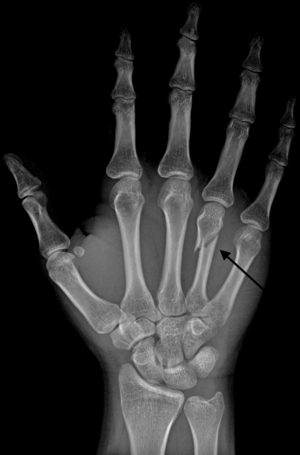

Boxer's fracture

- Fracture of the 4th or 5th metacarpal caused by an axial load, typically from punching a person or object

- Pain or swelling along the 4th or 5th metacarpals

- Volar angulation of metacarpal or "missing 4th/5th knuckle"

- AP and lateral hand xray